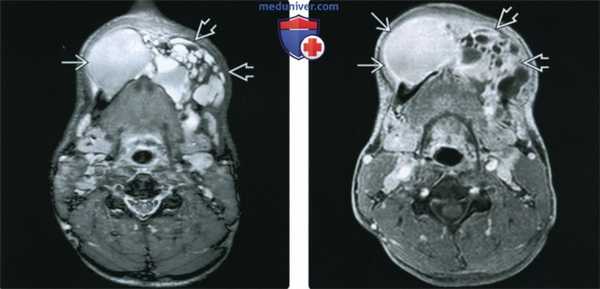

(Слева) На аксиальной МР-томограмме (STIR) визуализируется крупная амелобластома нижней челюсти, в составе которой находится массивный кистозный компонент (с правой стороны) с наличием уровней «жидкость-жидкость». Обратите внимание на многокамерный компонент с гиперинтенсивным сигналом на Т2ВИ (с левой стороны).

(Справа) При МРТ Т1ВИ FS сКУ в аксиальной проекции у это го же пациента с амелобластомой нижней челюсти определяется выраженное контрастное усиление стенок крупной однокамерной кисты, расположенной справа. Видны также множественные кисты меньшего размера с левой стороны.